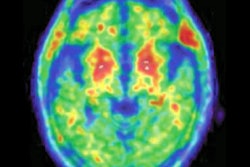

MRI scans of athletes with a history of concussion have shown changes in brain size, blood flow, and structural white matter months and even years after injury. Researchers have dug even deeper with PET scans to evaluate the brain's condition at autopsy and MRI scans to detect the loss of brain volume and the presence of atrophy in regions associated with CTE in living subjects.

Neither the brain of a noncontact-sport athlete (left) nor the brain of a contact-sport athlete (center) show enlarged ventricles or atrophied hippocampus, both of which have been associated with dementia. For comparison, the MRI at right is of a person with dementia and shows where abnormalities are located (arrows). Images courtesy of the Buffalo Neuroimaging Analysis Center.In one of the August 3 papers in JHTR, lead author Dr. Robert Zivadinov, PhD, along with Willer and colleagues, describe how they used 3-tesla MRI to investigate the volume of focal white-matter signal abnormalities, the volume of global and regional brain tissue structures, mean diffusivity fractional anisotropy, cerebral blood flow, and several other characteristics. Again, there were no significant differences in structural or functional MRI measures or in microscopic or macroscopic brain tissue injuries between the two sets of retired athletes.